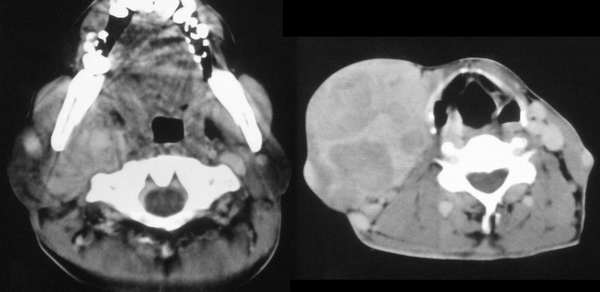

以下是引用wawaquan在2006-3-12 20:00:00的发言:[br]右颈部低密度包块,范围较大,内侧达咽侧壁,外侧达皮下,包绕颈部大血管;增强后明显不均匀强化。[br]男,42岁,颈部无痛性包块20年余,渐进性增大,近期疼痛。[br]考虑:淋巴血管瘤可能大。

以下是引用usa911go在2006-3-12 20:02:00的发言:[br]右侧颈部占位性病变,强化明显,血管有包饶,无钙化,其内有坏死灶。考虑淋巴瘤

以下是引用逸风在2006-3-12 21:02:00的发言:[br]肿瘤!可能来源于腮腺!

以下是引用hzw19711230在2006-3-12 21:52:00的发言:[br]颈部神经源性肿瘤